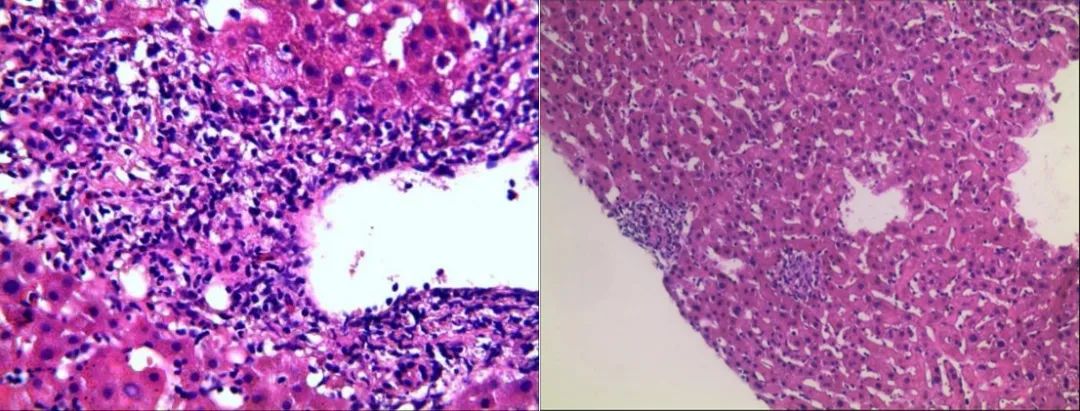

2022-11-21行肝穿活检: 肝组织结构大致正常,未见淤胆及脂变,肝实质散在点状坏死灶及慢性小肉芽肿结节分布;全切片查见5个较为完整的汇管区,小胆管轻度扩张,数目不增加,管周较多淋巴细胞、浆细胞及少量中性粒细胞浸润,侵蚀界面,个别汇管区组织细胞聚集、小肉芽肿形成。考虑特发性肉芽肿性肝炎。免疫标记:CD34(灶+)、CK19(小胆管+)、HbsAg(-)(图2)。

图2. 行右肝穿刺,肝组织结构大致正常,未见淤胆及脂变,肝实质散在点状坏死灶及慢性小肉芽肿结节分布;全切片查见5个较为完整的汇管区,小胆管轻度扩张,数目不增加,管周较多淋巴细胞、浆细胞及少量中性粒细胞浸润,侵蚀界面,个别汇管区组织细胞聚集、小肉芽肿形成。

该患者肝酶表现为ALP、γ-GT明显升高,而ALT、AST轻度升高,且梅毒血清学实验阳性,肝炎病原学、自身免疫性肝炎抗体等检查全阴性;肝脏病理示:小胆管轻度扩张,数目不增加,管周较多淋巴细胞、浆细胞及少量中性粒细胞浸润,侵蚀界面,个别汇管区组织细胞聚集、小肉芽肿形成。因此在排除药物、自身免疫等其他可能原因,该患者考虑梅毒感染导致肝损害可能性大。